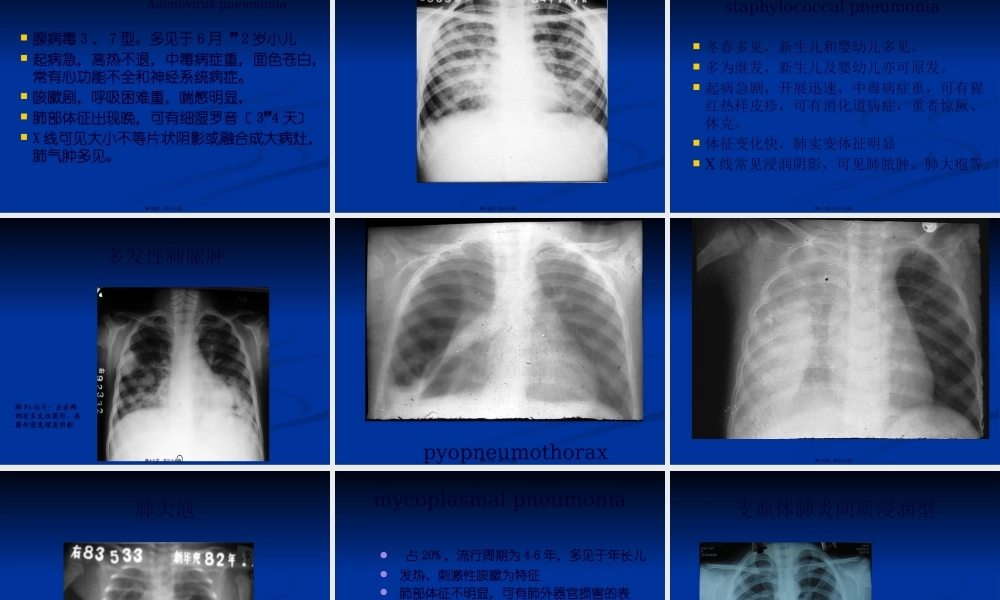

0下载

二年级数学下册期末质检卷(苏教版)二年级数学下册期末质检卷(苏教版)#期末复习 #期末测试卷 #二年级数学 #二年级数学下册#关注我持续更新小学知识.pdf

10.00金币

二年级数学下册期末混合运算专项练习二年级数学下册期末混合运算专项练习#二年级#二年级数学下册#关注我持续更新小学知识 #知识分享 #家长收藏孩子受益.pdf